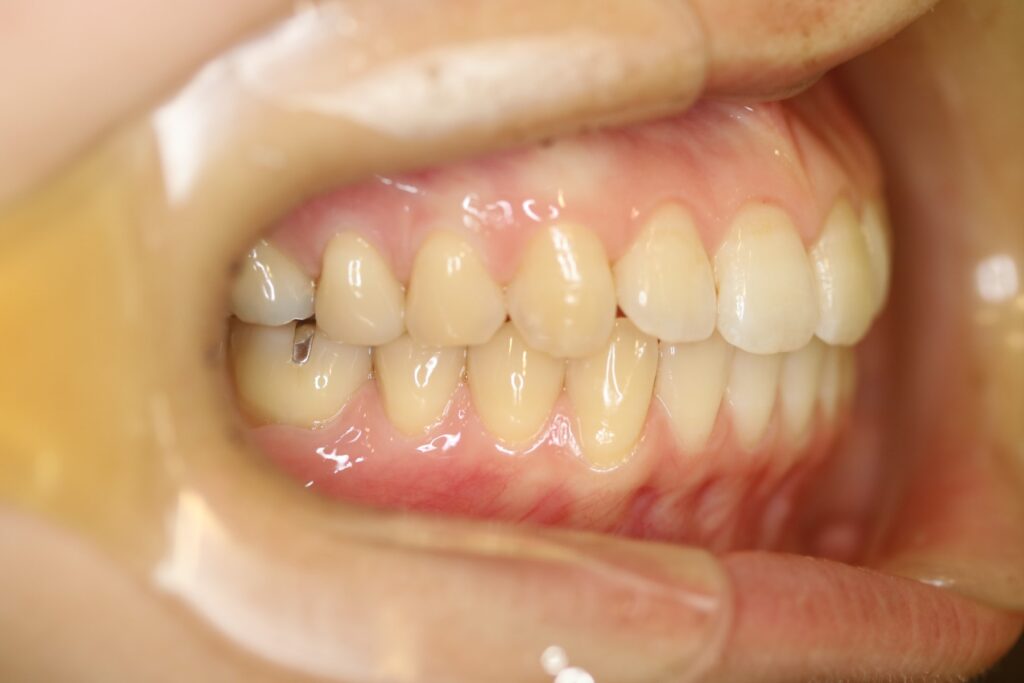

治療実績(症例) アライナー矯正 症例1 上顎前突症例 症例2 上下顎前突症例 症例3 叢生 症例4 開咬 症例5 開咬(外科的矯正治療) アライナー矯正 Post Share Hatena Line RSS feedly Pin it note 1.主訴2.診断名3.初診時年齢4.治療に用いた主な装置とオプション5.抜歯部位6.治療期間・通院回数7.総額と費用内訳総額相談検査・診断料調整料4,000円8.リスク・副作用 治療前 治療中 治療後